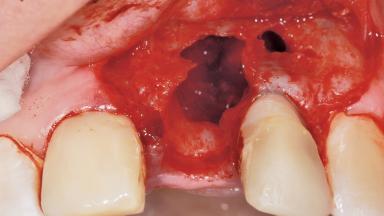

Late Flapless Placement of an Implant in a Maxillary Left Central Incisor Site

A 39-year-old male patient presented with a chief complaint of discomfort and gingival discoloration around his maxillary left central incisor. He was in good general health and was a non-smoker. His past dental history was significant because of the traumatic fracture of tooth 21 in a sporting accident at age 13. Initial dental treatment included endodontic therapy and a full-coverage restoration. The patient became symptomatic 5 years later, when structural failure of the tooth resulted in the dislodgment of the crown. Endodontic retreatment, apical surgery, and post-and-core restoration were performed.

Bone Volume Deficient horizontally, requiring prior grafting

Bone Augmentation Horizontal|Staged